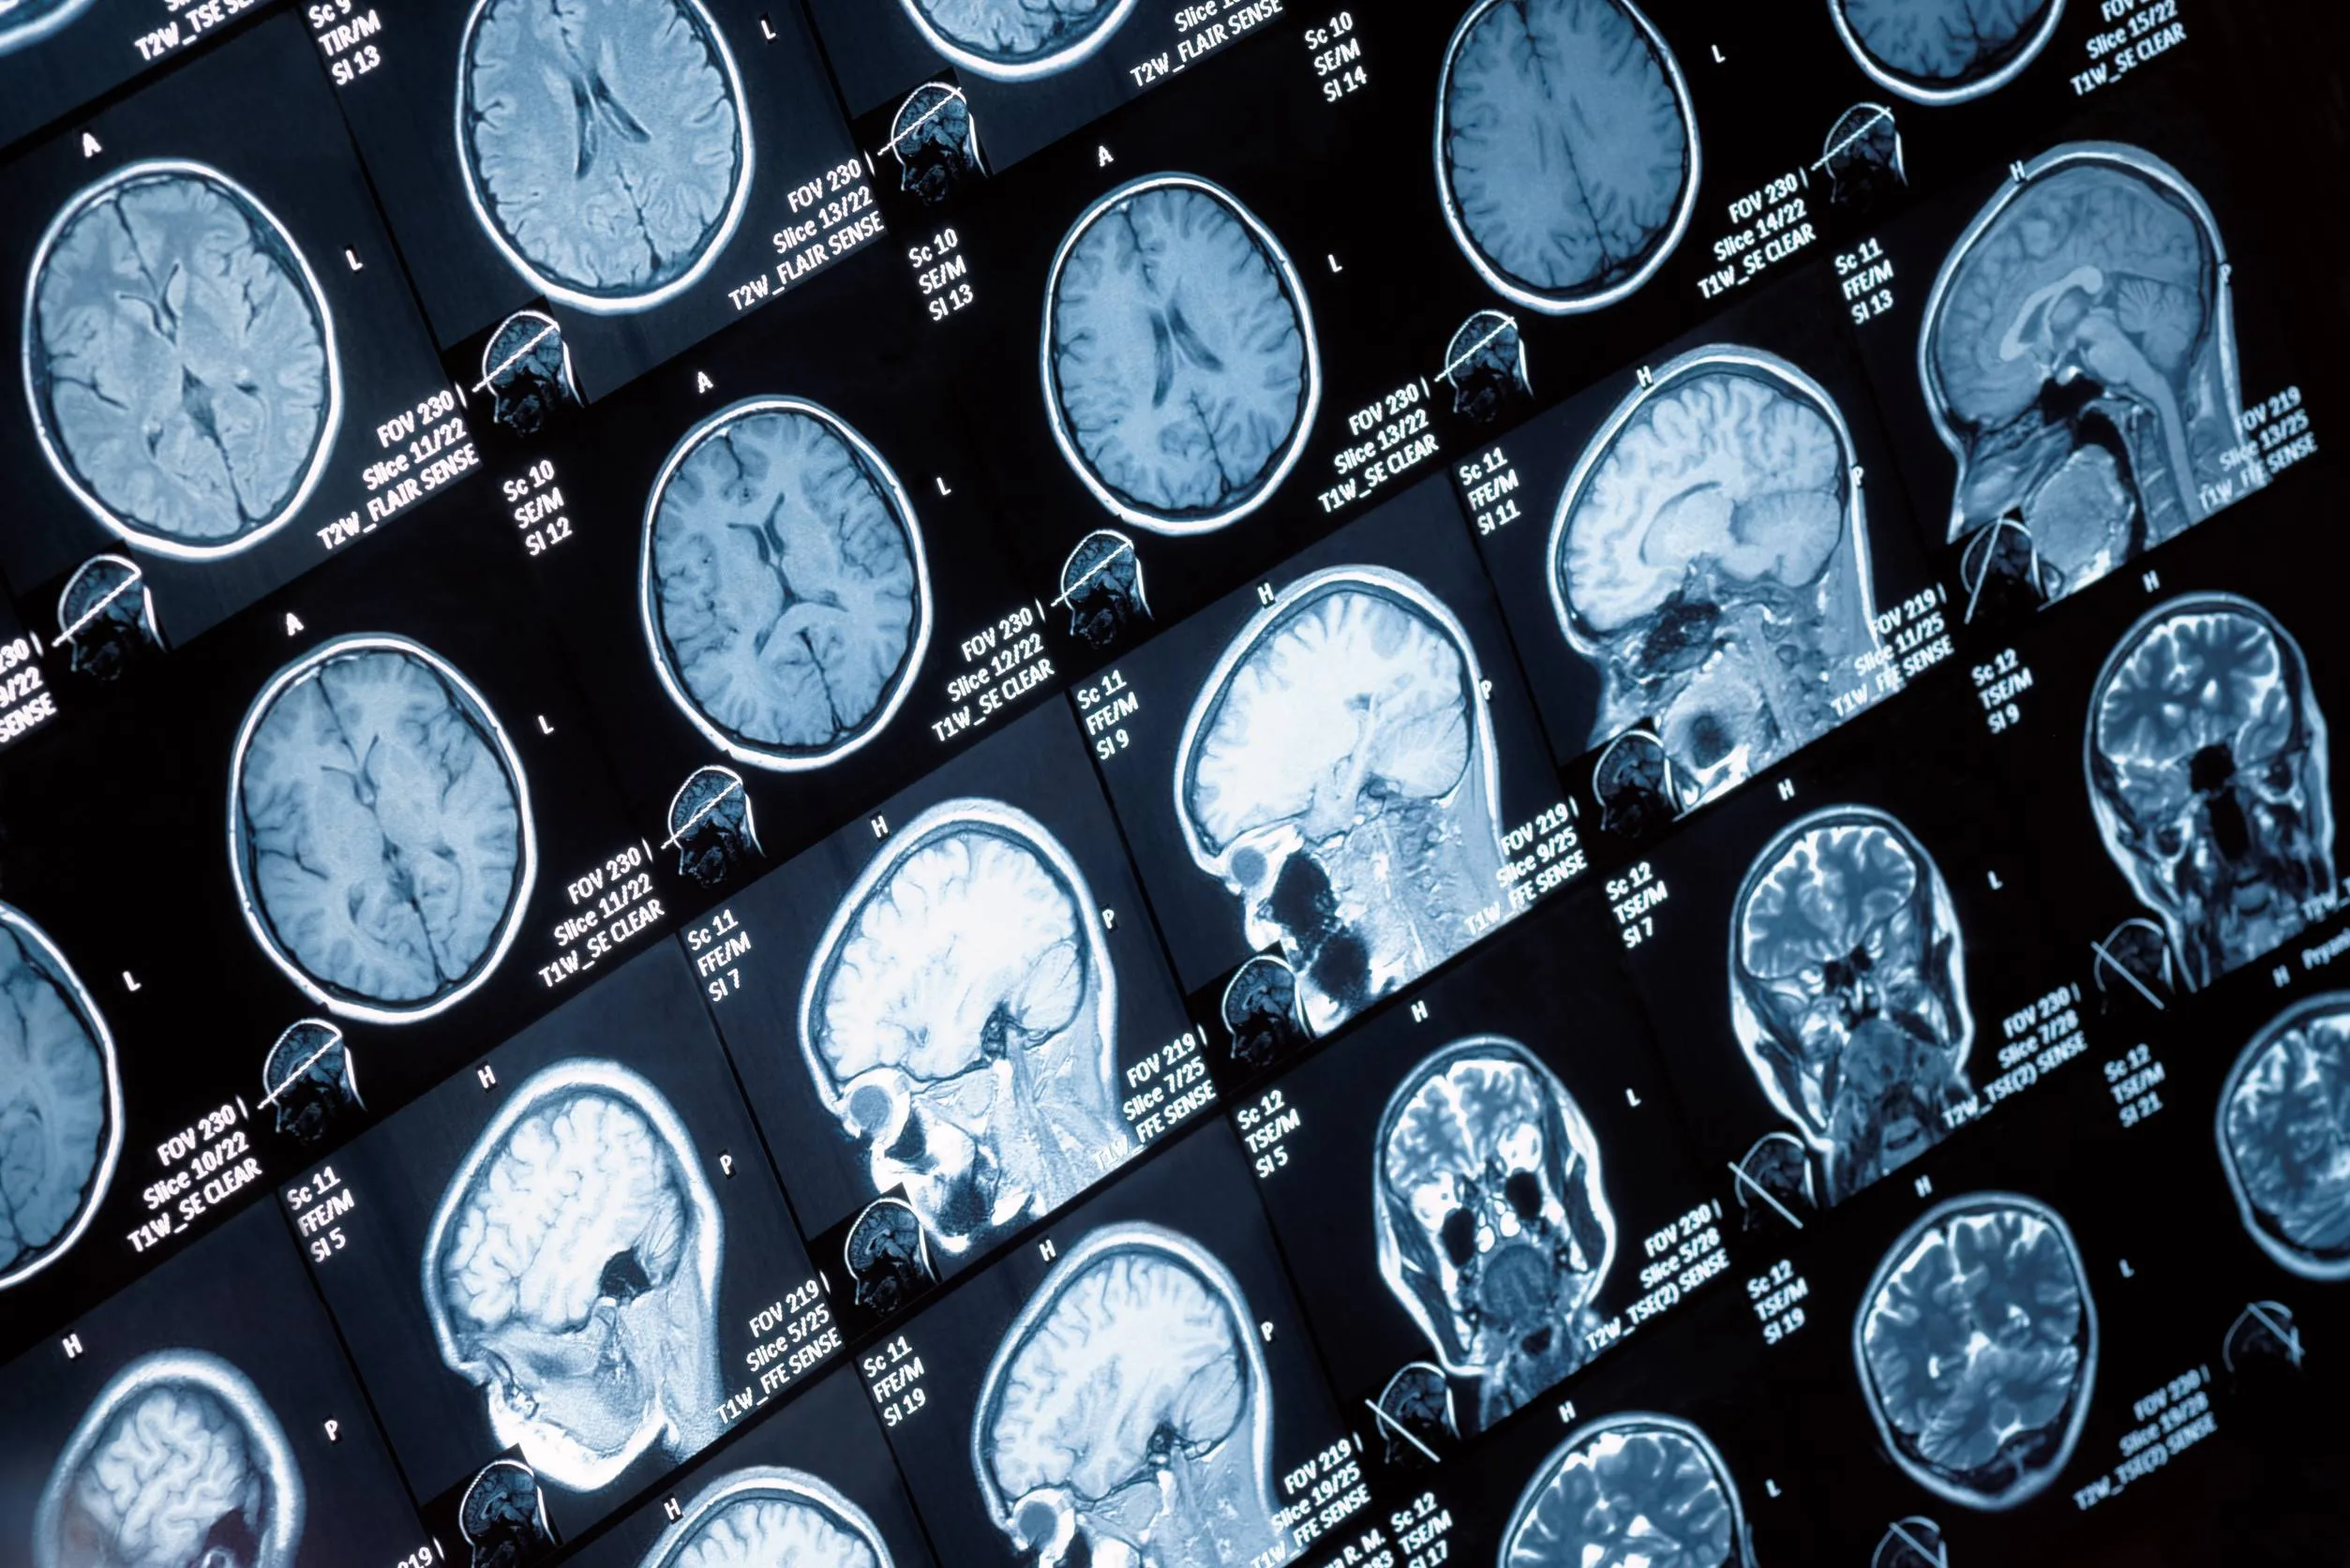

Glioblastoom, een van de dodelijkste soorten hersentumoren, doet iets angstaanjagends met je schedel. Wetenschappers hebben ontdekt dat deze agressieve kanker niet alleen het hersenweefsel aantast, maar ook het omliggende bot vernietigt en dat gebeurt zelfs op plekken ver van de tumor zelf.

De wetenschappers ontdekten dit eerst in muizen met hersentumoren. Ze gebruikten speciale scantechnieken om de schedels tot in detail te bekijken. Het bot werd dunner en poreuzer, vooral langs de schedelnaadlijnen. Dat zijn de lijnen waar de verschillende schedelbeenderen aan elkaar zitten. Zelfs het achterhoofdsbeen, een stuk ver weg van waar de tumor zat, werd aangetast.

Om te controleren of dit ook bij mensen gebeurt, bekeken de wetenschappers CT-scans van 26 patiënten met glioblastoom. Ze vergeleken deze met scans van mensen zonder hersentumor maar van dezelfde leeftijd en hetzelfde geslacht. En inderdaad: bij de kankerpatiënten was de schedel veel dunner op precies de plekken waar bij muizen ook de grootste afwijkingen waren gezien.